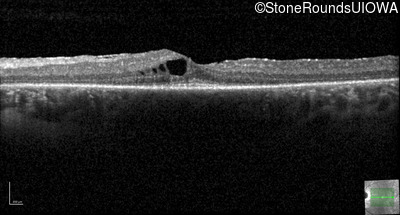

Optical Coherence Tomography - Right -

20/20 -1

Exemplar / OCT Stack